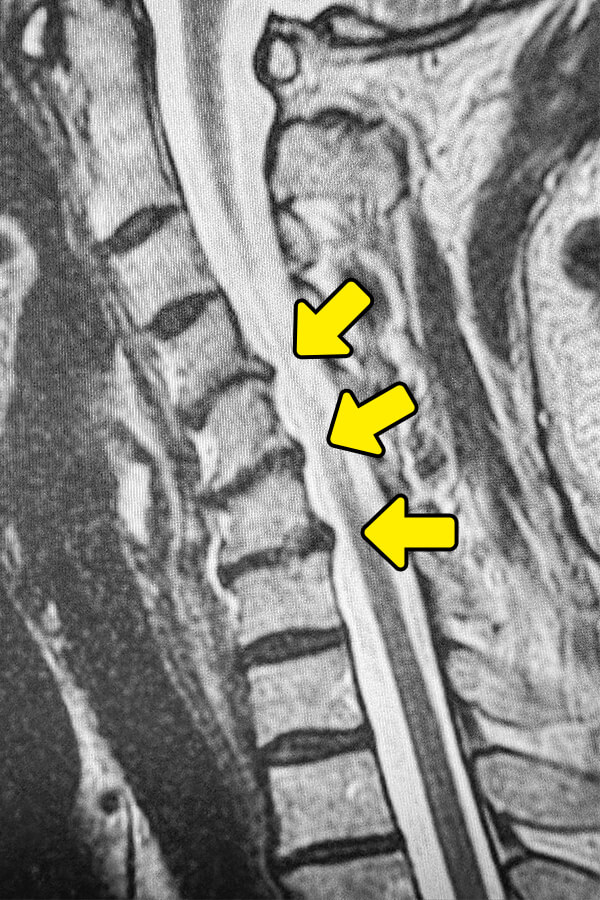

5年以上前より頚部痛と慢性の肩こりがありましたが、今年になって肩甲骨付近まで鈍痛が広がっておられます。ストレスが原因だと考え放置していましたが、今回、親戚の方が当院で頚椎治療を受けられた縁から受診されています。MRI検査では、C4/5、C5/6、C6/7に存在する椎間板に変形が見られ、容量も減少気味であり、ヘルニアも認めます。頚椎椎間板変性症と判断しました。頚部から肩甲骨にかけての疼痛原因となります。ディスクシール治療の有効率は84%と高く、有益である事をご説明し治療となりました。治療時間は15分で、患者様は鎮静剤を使用するため痛みや不安を感じられることはありませんでした。

椎間板の高さの減少、骨棘の有無、頚椎のアライメント(並び)を確認。 - MRI検査

椎間板の水分量、線維輪の亀裂、神経の圧迫状態を詳細に確認。変性した椎間板はMRIで黒く映る(正常は白い)。変性の程度の評価に最も重要。

MRI検査では、正常な椎間板は白く明るく映り、変性した椎間板は黒く暗く映ります。これは椎間板内の水分が減少し、クッション機能が低下していることを表します。しかし、画像上の変性があっても、無症状の方もおられます。痛みやしびれがある場合は治療の対象となりますので、専門医による診察が重要です。当院ではMRI画像で来院前に治療の可否が分かる無料画像相談を行っておりますので、是非ご利用ください。